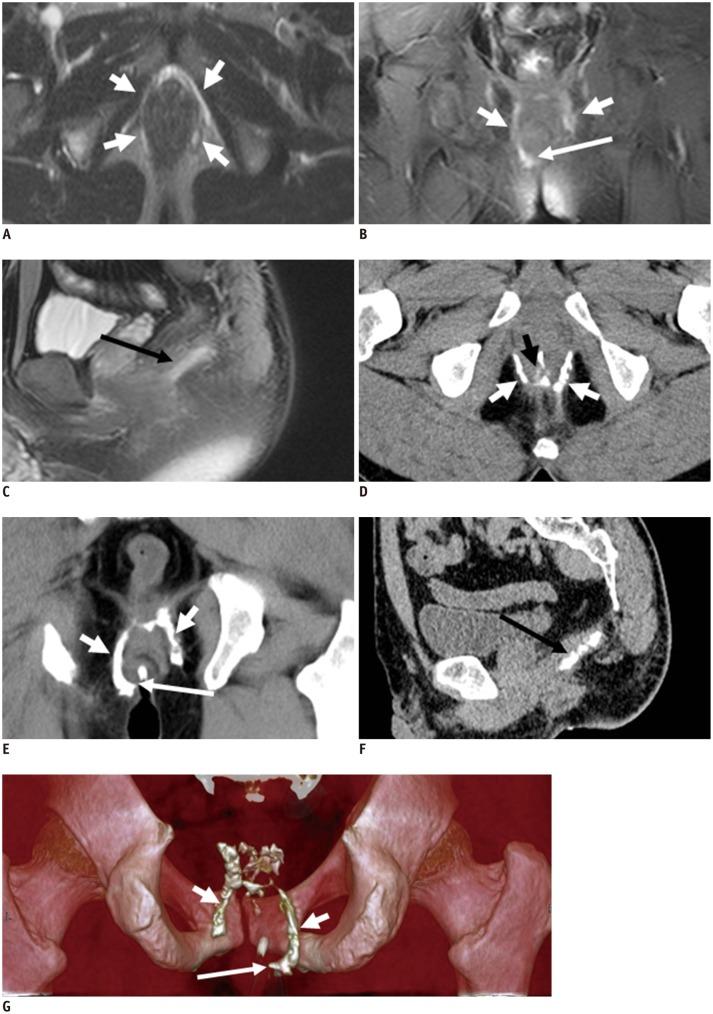

Imaging of anal fistulas: comparison of computed tomographic fistulography and magnetic resonance imaging.

The primary importance of magnetic resonance (MR) imaging in evaluating anal fistulas lies in its ability to demonstrate hidden areas of sepsis and secondary extensions in patients with fistula in ano. MR imaging is relatively expensive, so there are many healthcare systems worldwide where access to MR imaging remains restricted. Until recently, computed tomography (CT) has played a limited role in imaging fistula in ano, largely owing to its poor resolution of soft tissue. In this article, the different imaging features of the CT and MRI are compared to demonstrate the relative accuracy of CT fistulography for the preoperative assessment of fistula in ano. CT fistulography and MR imaging have their own advantages for preoperative evaluation of perianal fistula, and can be applied to complement one another when necessary.